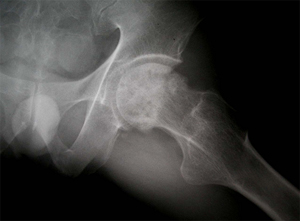

상기 환자는 46년 전부터 고관절 통증이 있었으며, 12년전 Lt. total hip replacement(THR)을 받은 분으로 2년 전부터 통증으로 인해 물리치료를 받았지만 통증이 지속되었고, 본원 OS 외래에서 방사선 촬영하여 Lt. THR loosening 소견으로 revision O.P. 위해 입원하여 O.P.이후 재활위해 물리치료실로 의뢰됨

수술 전 고관절 X-선 사진